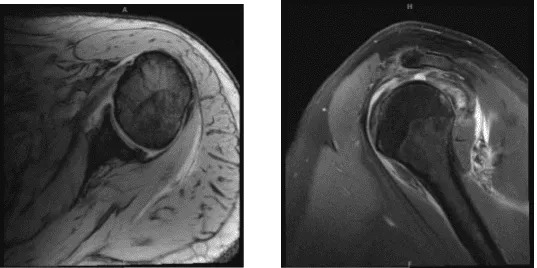

Tras realizar una resonancia magnética, se descubrió que el supraespinoso e infraespinoso del hombro izquierdo estaban completamente desgarrados. También se notó la ausencia del tendón del bíceps.

MRI-3T Hombro izquierdo sin contraste